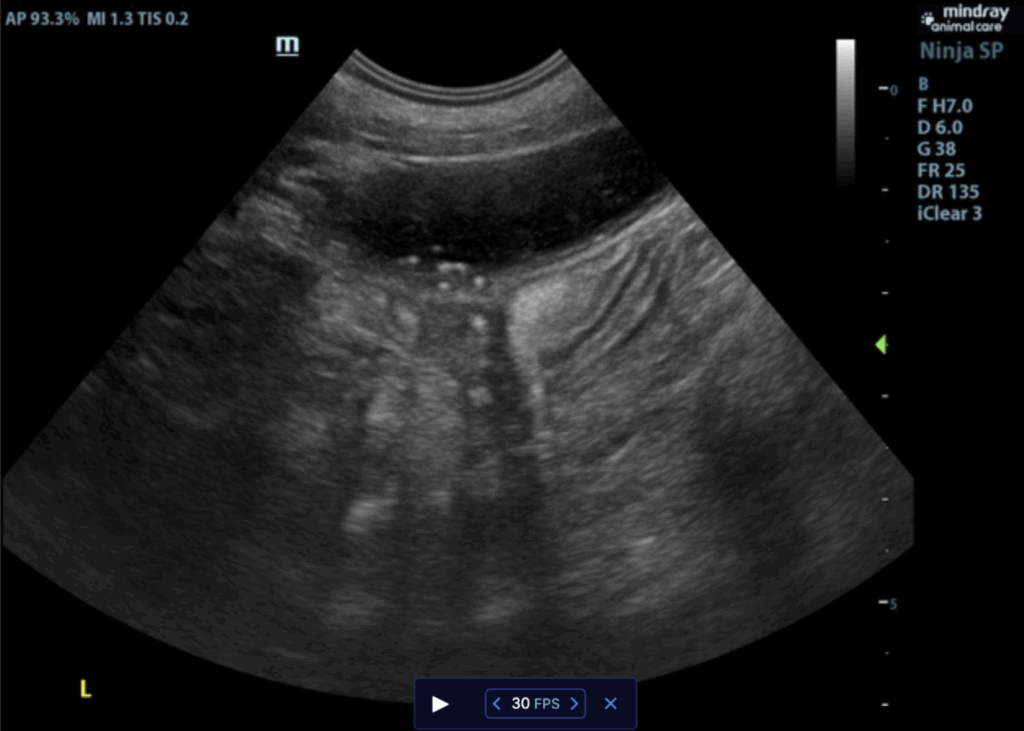

ULTRASONOGRAPHIC EXAMINATION OF THE ABDOMEN

Liver:

The liver was mildly subnormal in size. The hepatic parenchyma was uniform, yet hypovascular owing to the extrahepatic shunting. The extrahepatic shunt decoursed ventral caudally and then dorsally. It appeared to bypass the vena cava and aorta. It likely entered into the azygos, however, the termination

could not be found given the lack of acoustic window. The hepatic width was approximately 2.0 cm in short axis. The portal vein was subnormal in size and measured 0.34 cm after the gastroduodenal vein junction. An extrahepatic vessel was present just caudal to the pylorus and measured 1.05 cm. This is

consistent with gastric shunt. The aorta and vena cava both measured approximately 0.65 cm. The gallbladder and common bile were unremarkable.

ULTRASONOGRAPHIC FINDINGS

- Extrahepatic portosystemic shunt. Gastroazygos or gastrophrenic shunt is suspected.